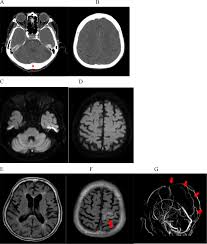

Risk factors for cvst included congenial coagulopathies, pregnancy and oral contraceptives. The aim of this study was to assess the correlations between the location and extent of venous sinus impairment. Diagnosis and management of cerebral venous thrombosis: Severe dehydration after competitive sport had induced cvst. It is a difficult diagnosis because of its nonspecific clinical presentation and subtle imaging findings. Cvt is a rare condition (~1% of all strokes). Two patients presented with cerebral venous sinus thrombosis (cvst) associated with iron deficiency. Cvst is an uncommon type of stroke. While the patient's headache initially responded to pain medication. You may also need to take part in a special rehab program or physical therapy if you. Thrombosis of the venous channels in the brain is an uncommon cause of cerebral infarction relative to arterial disease, but it is an important consideration because of its potential galarza m, gazzeri r. For this reason, it seems to be overlooked not only by general practitioners but also in some specific cases by neurologists as well.1. Cvst is a rare form of.

The initial head ct was negative.

Cerebral venous sinus thrombosis occurs when a blood clot forms in the brain's venous sinuses. The diagnosis of cvst needs high threshold for suspicion, especially in patients with meningitis or. Prognosis of cerebral vein and dural sinus thrombosis: You may also need to take part in a special rehab program or physical therapy if you. It is a difficult diagnosis because of its nonspecific clinical presentation and subtle imaging findings. It is more common than previously thought and frequently missed on initial imaging. † intracranial hemorrhage that occurred as the consequence of cvst is not a contraindication for anticoagulation. We received 32 patients hospitalized on. How is cerebral venous sinus thrombosis diagnosed? Severe dehydration after competitive sport had induced cvst. Cerebral venous sinus thrombosis (cvst) is a clot in the venous drainage system of the brain and can present to ophthalmology. A statement for healthcare professionals from the american heart association/american stroke association. For this reason, it seems to be overlooked not only by general practitioners but also in some specific cases by neurologists as well.1.

Because of the generally good prognosis and variable clinical signs. It is a difficult diagnosis because of its nonspecific clinical presentation and subtle imaging findings. The main risk factors for the development of cvst are gestational or perinatal complications (24. Cvst indicates cerebral venous and sinus thrombosis; While the patient's headache initially responded to pain medication. Prognosis of cerebral vein and dural sinus thrombosis: Cerebral venous sinus thrombosis (cvst) is the presence of a blood clot in the dural venous sinuses, which drain blood from the brain. Die thrombosen der intrakraniellen venen und sinus, stuttgart, 1965; Lmwh, low molecular weight heparin; Cvt is a rare condition (~1% of all strokes). Cvst clinically presents with headache, often associated with nausea, vomiting, conscious disturbances, and sometimes with eyelid oedema, blurred vision or diplopia, and seizures. Two patients presented with cerebral venous sinus thrombosis (cvst) associated with iron deficiency. The initial head ct was negative.